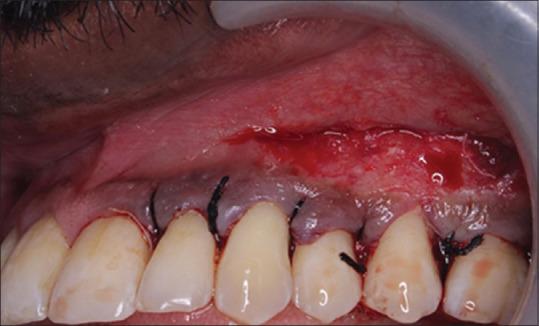

使用黏膜移植术治疗附着龈宽度不足

Management of inadequate width of attached gingiva using mucograft.

Attached gingiva around the teeth is crucial in preserving periodontal health. Plaque development and soft-tissue recession are both prevented by adequate attached gingiva. The processes for harvesting soft-tissue grafts are frequently accompanied by some level of morbidity which results in commercially available xenogeneic collagen matrices. The blood clot is more effectively stabilized by this collagen matrix, which also promotes vascularization. Furthermore, this biomaterial enhances root coverage and keratinized gingiva regeneration in both width and thickness. The purpose of the case report is to increase the width of attached gingiva using Mucograft. This case report highlights a case scenario where a patient presented with probing depth of 6-8 mm in relation to 24, 25, 26, 27, and 28, Grade I mobility in relation to 25.26, and 1 mm of the width of attached gingiva in relation to 25, 26, and 27. Flap surgery was done and simultaneously vestibular deepening was done in relation to 25, 26, and 27, and mucograft was placed and stabilized. On a 3-month follow-up, probing pocket depth was 3 mm and 4 mm of width of the attached gingiva was seen in 25, 26, and 27. The Mucograft was beneficial in this clinical case for the purpose of extending the width of the associated gingiva, making it a feasible treatment option for soft-tissue augmentation.

牙齿周围的附着龈对于保持牙周健康至关重要。充足的附着龈可预防菌斑形成和软组织退缩。获取软组织移植物的过程常常伴随着一定程度的发病率,这导致了市售的异种胶原基质的出现。这种胶原基质能更有效地稳定血凝块,还能促进血管化。此外,这种生物材料可增强牙根覆盖以及角化龈在宽度和厚度上的再生。该病例报告的目的是使用Mucograft增加附着龈的宽度。本病例报告突出了这样一个病例情况:一名患者24、25、26、27和28号牙的探诊深度为6 - 8毫米,25、26号牙为I度松动,25、26和27号牙的附着龈宽度为1毫米。进行了翻瓣手术,同时对25、26和27号牙进行了前庭加深,并放置并固定了Mucograft。在3个月的随访中,25、26和27号牙的探诊袋深度为3毫米,附着龈宽度为4毫米。在这个临床病例中,Mucograft对于增加相关牙龈的宽度是有益的,使其成为软组织增量的一种可行治疗选择。